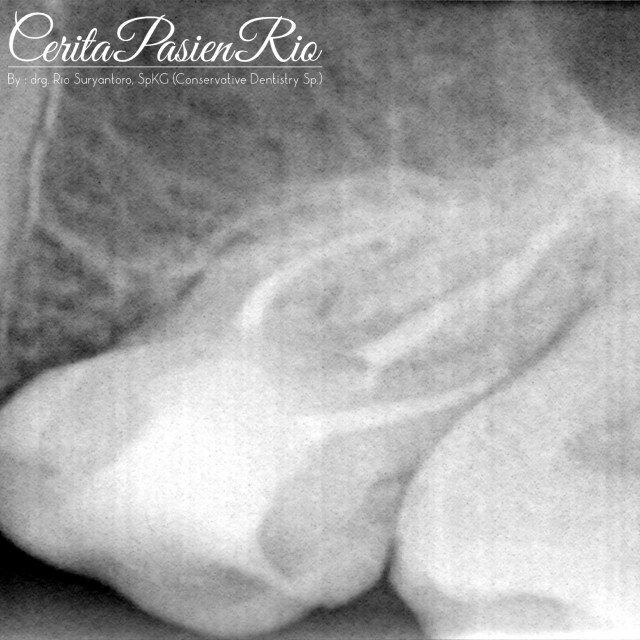

pertama-tama saya lakukan anestesi dan pemasangan rubber dam (Nictone Ruber Dam). sambil dalam hati saya berpikir “kenapaaa ya kok beberapa dokter gigi sempat tidak melihat adanya crack itu? padahal kan jelas ada garis di marginal ridge? oklusinya juga berat.. hmm…” lalu saya coba melihatnya lagi..

lalu saya berkata dalam hati lagi “ooooh.. mungkin, karena operator sebelumnya tidak menggunakan lup, sehingga tidak melihat garis itu secara jelas..” karena, setelah saya pakai lup, maka keadaannya akan seperti ini..

Nah, bener kan.. untuung pakai lup! hehe..